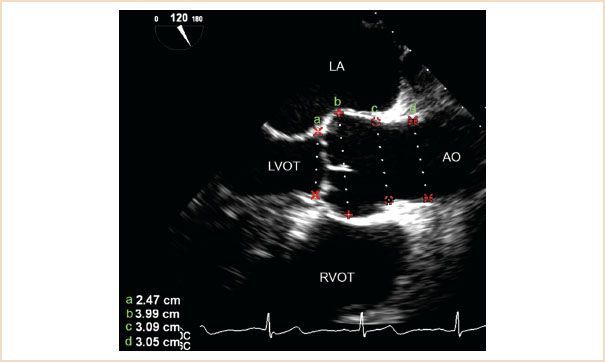

Label a, b, c, d

aortic annulus (a)

sinus of Valsalva (b)

sinotubular junction (c)

proximal ascending aorta (d)

What is a normal Aortic Annulus Size?

1.8-2.3 cm (18 - 23 mm)

What aortic valve coronary cusps are seen on the ME Aortic Valve LAX View?

Right coronary cusps is at the bottom of image (Anterior structures are more towards the bottom of the image)

NCC or LCC are at the superior aspect of the image (These are posterior structures)